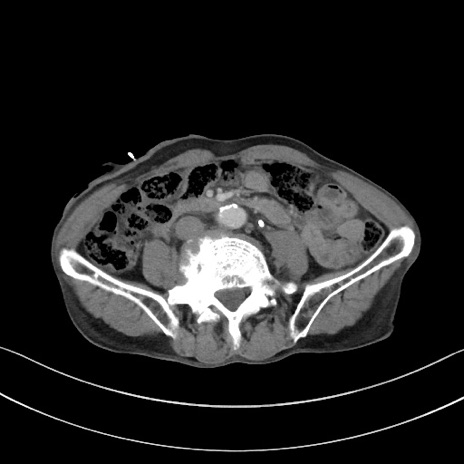

症例3(横断像)

【症例】 70歳代男性

【主訴】右鼠径部腫瘤、疼痛

【現病歴】本日朝より上記主訴あり、受診。

【既往歴】膀胱癌にて膀胱全摘、両側尿管皮膚瘻

【データ】WBC 5600、CRP 0.56